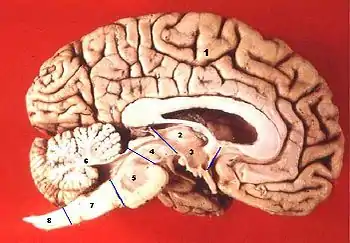

1. Полушарие большого мозга (конечный мозг)

2. Таламус (промежуточный мозг)

3. Гипоталамус (промежуточный мозг)

4. Средний мозг

5. Мост

6. Мозжечок

7. Продолговатый мозг

8. Спинной мозг